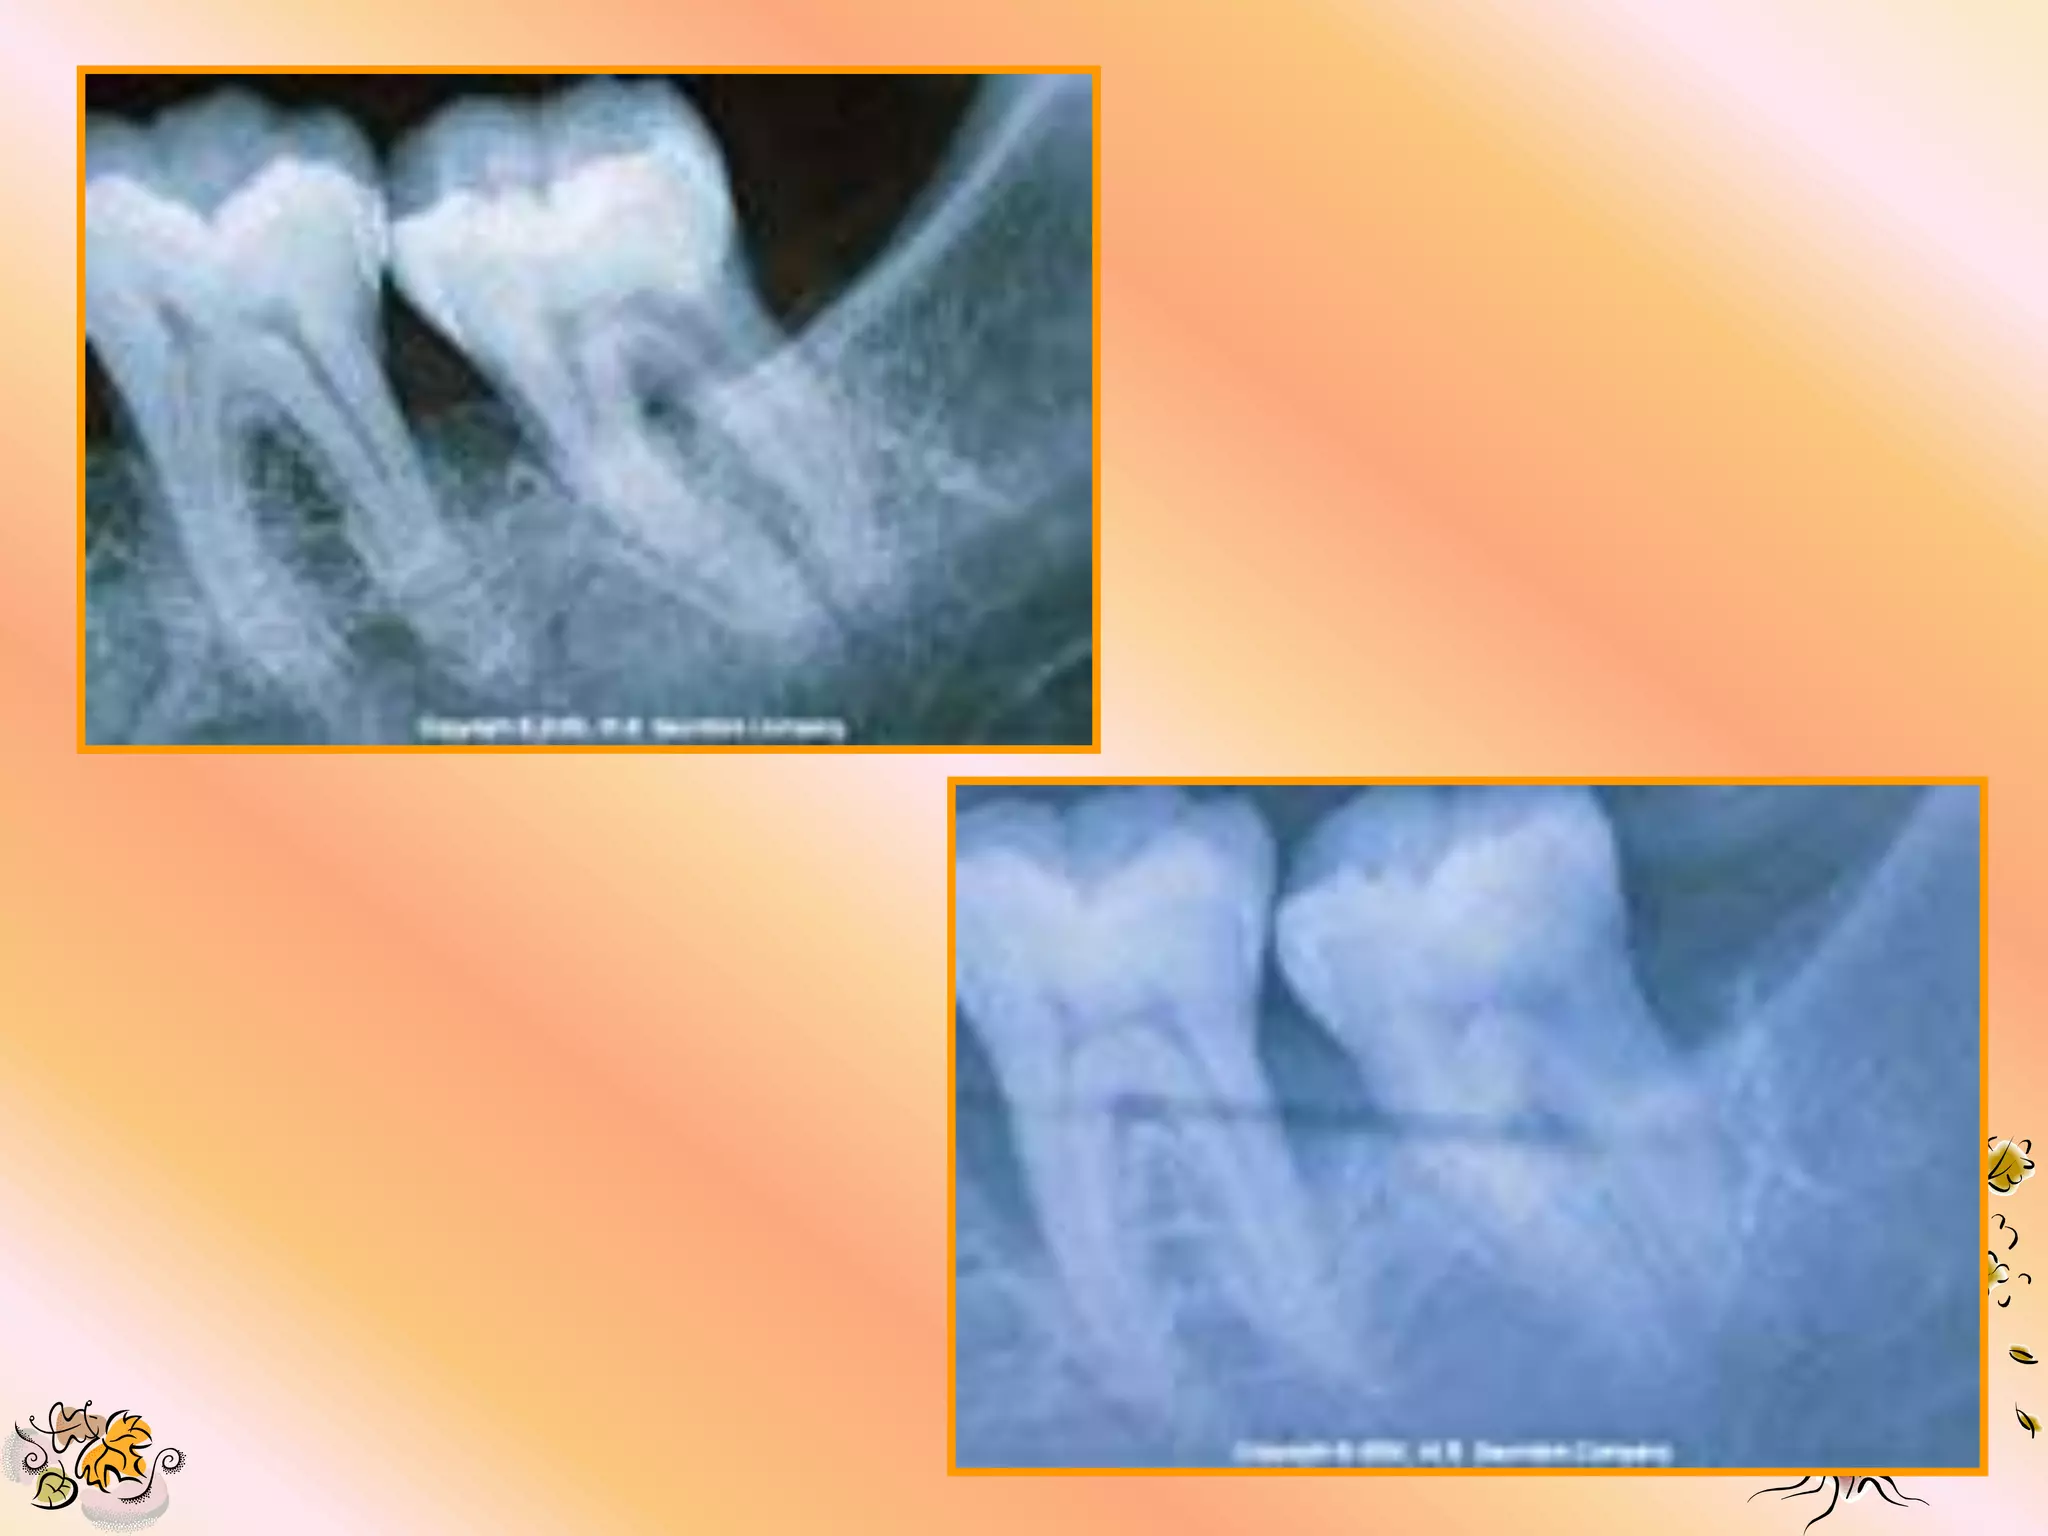

INDICATIONS

1. Class II furcation

2. Infra bony defect.

3. Recession defect

4. To restore PD attachement in narrow 2

or 3 walled infra bony defect.

5. Alveolar ridge augmentation

6. Repair of apicocetomy defect.

DEFECT SELECTION

• It may have the greatest impact on the

predictability of the regenerative regions.

A). MOST PREDICTABLE:-

1. for grade II furcation on teeth with high

interproximal bone.

2. 2 to 3 wall intra bony vertical defect >4-5

mm. measurable defect.

B). MODERATE PREDICTABILITY:-

1. 2 wall defect.

2. Maxillary mesial or distal ClassII furcations.

C). LOW PREDICTABILITY:-

1. Class III furcation with high interproximal

bone.

D). LEAST PREDICTABLE:-

1. Horizontal bone loss.

2. Class III furcation with horizontal bone loss